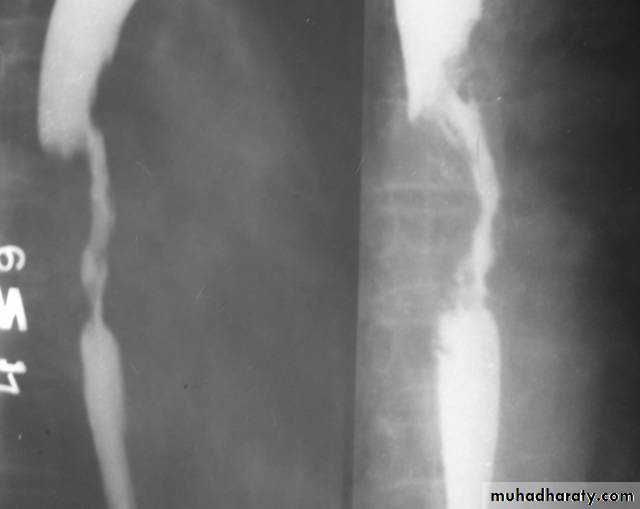

Narrowing :

1-the narrowing is Constant Short length (confined to cardia).

2-Regular and smooth.

3- No shouldering sign.

4-Tapering (Tip of pencil , cigar shape) Under left dome of diaphragm.

Achalasia continue

5. DILATATION (Sac like in proximal part )6-Undulating or spiky out line due to sluggish peristalsis.

7 Non- homogeneity of Barium due to food particles.

8-Air Barium level.